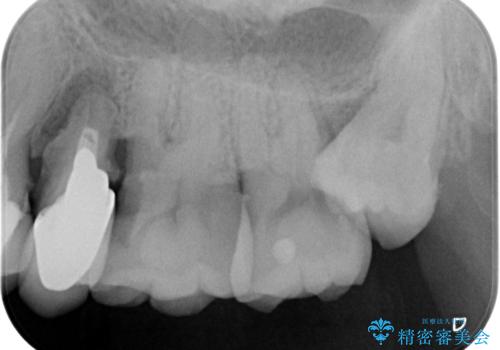

X線、歯周組織検査の結果、残すことができない歯周病の進行が左上小臼歯に認められました。

抜歯後は、インプラントではなくブリッジを選択されました。

最終的なブリッジの清掃性を高めるため、歯ぐきのボリュームがこれ以上減少しないよう抜歯時に歯槽堤保存術を行うような工夫をしています。